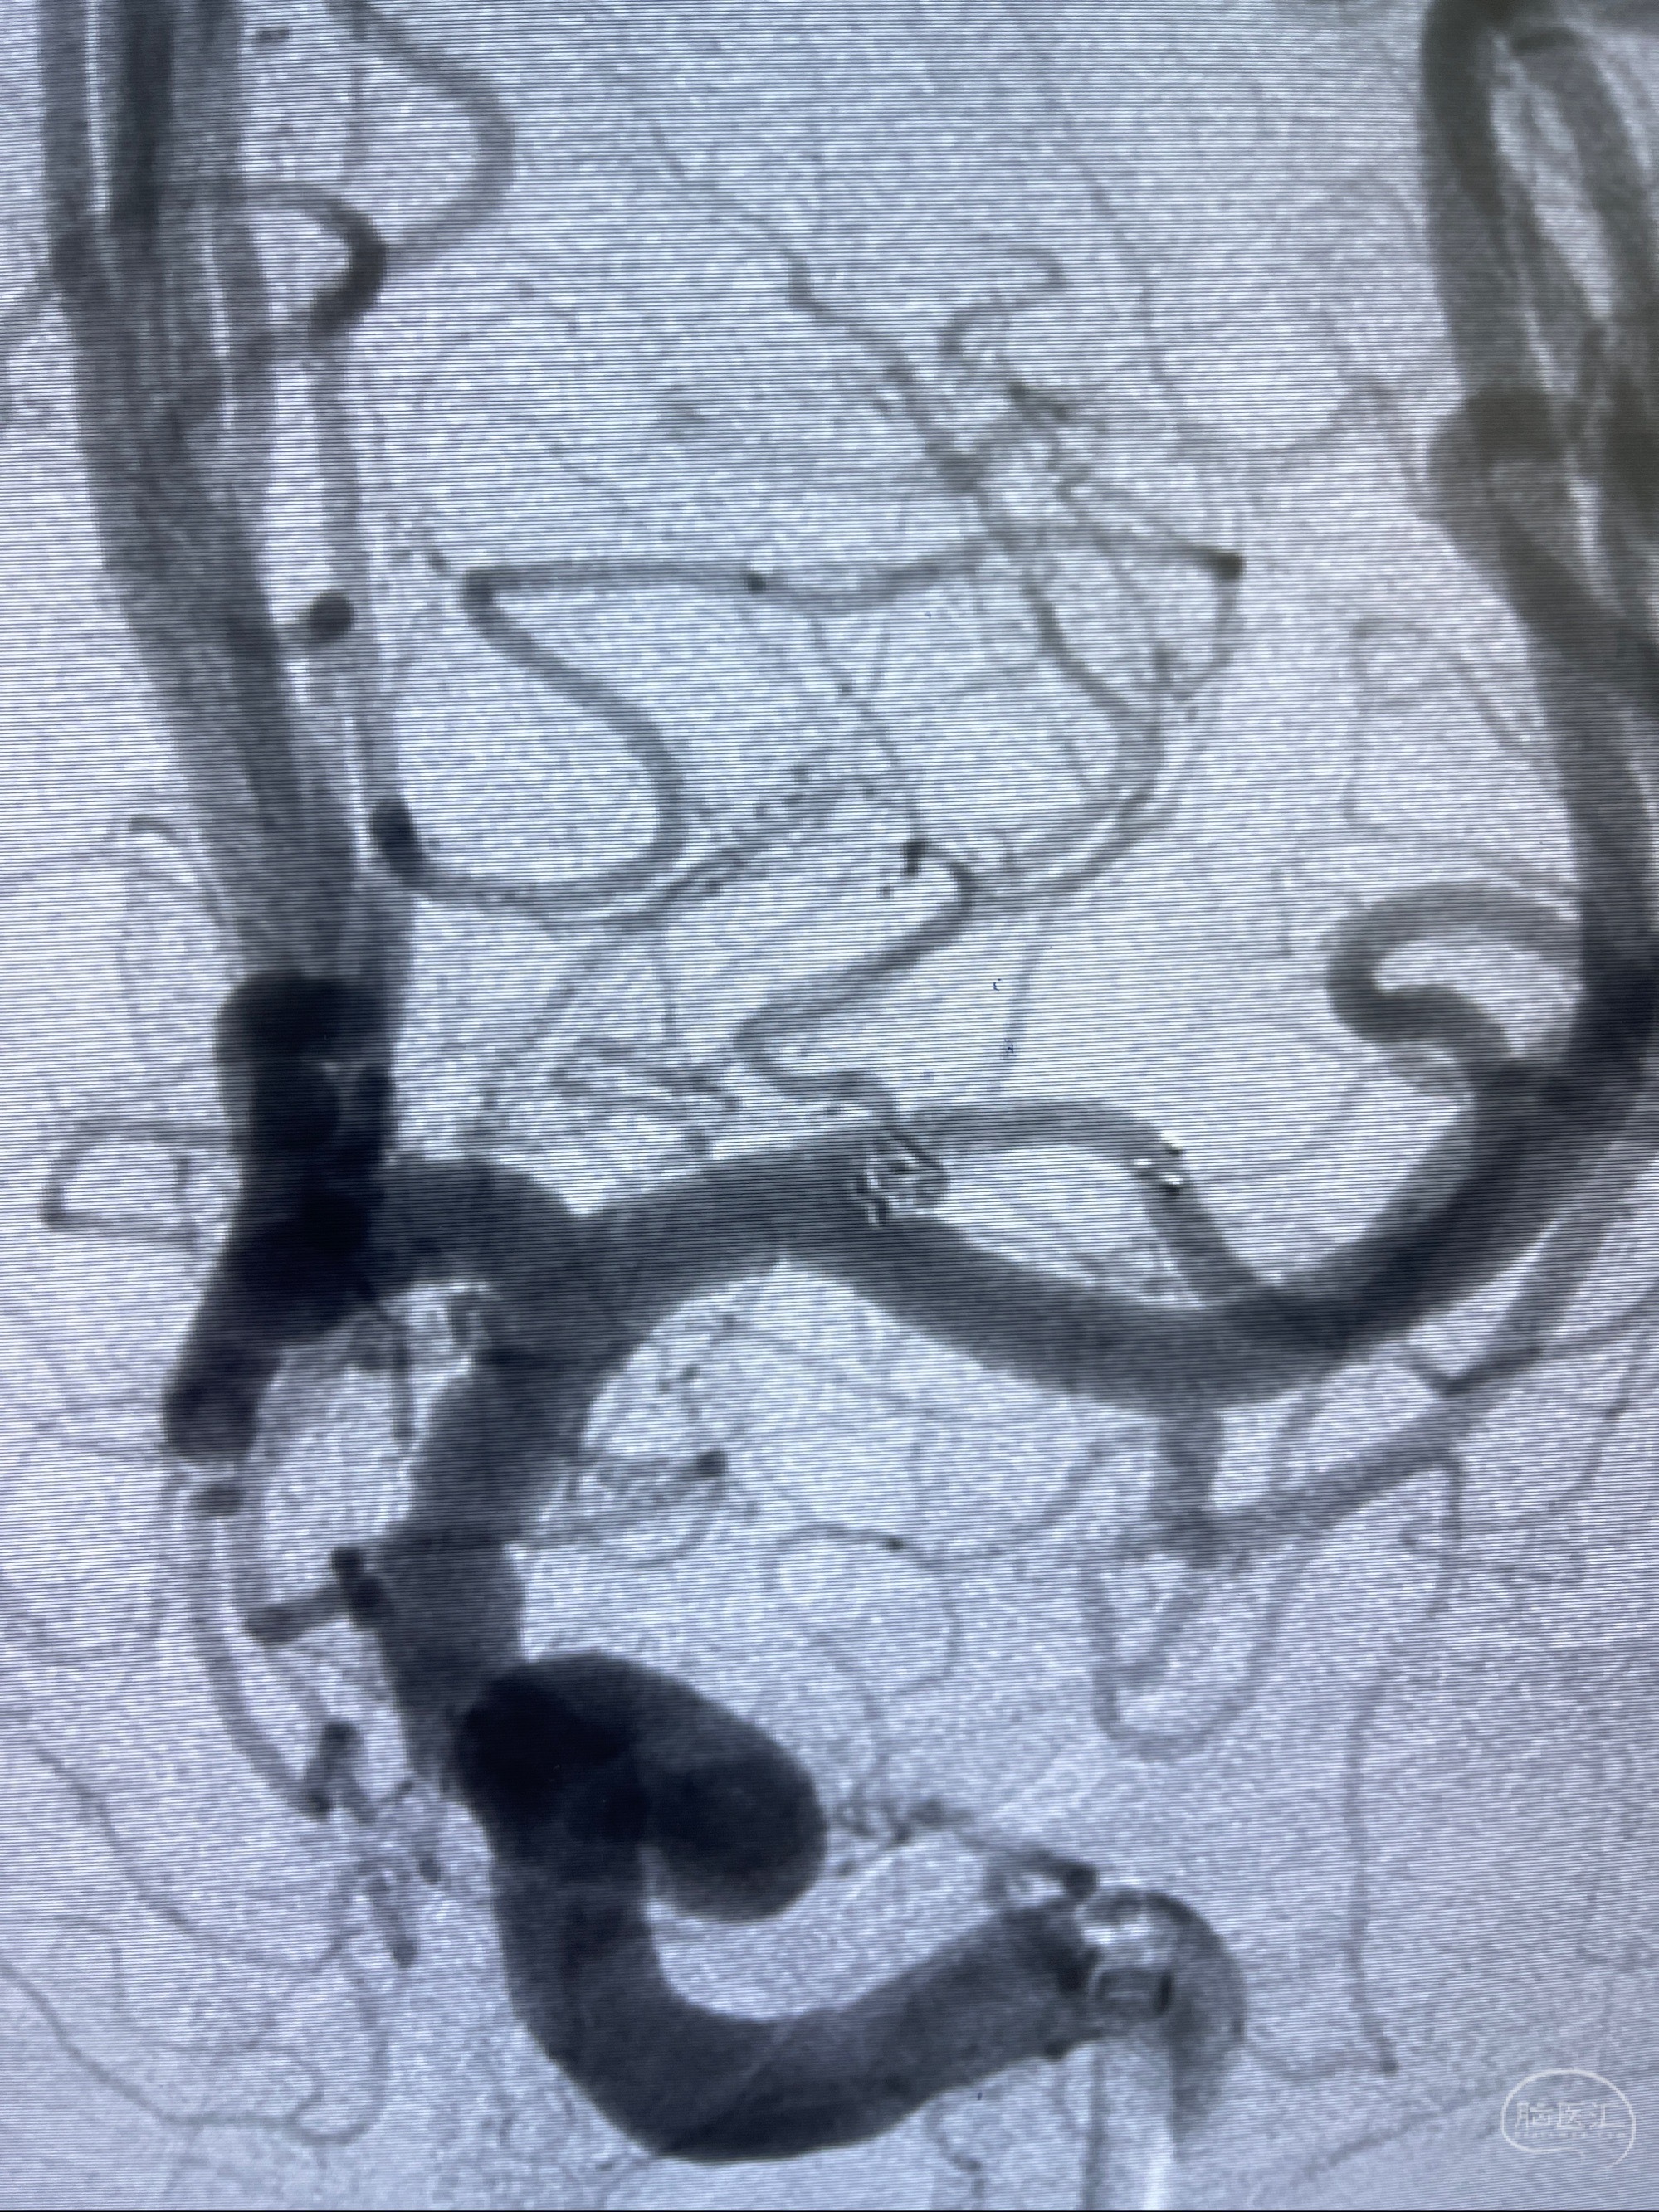

2023-08-14DSA:

左侧大脑中动脉动脉瘤,约2.6-2.8-3.4-2mm大小(瘤颈部、瘤体部、瘤高)